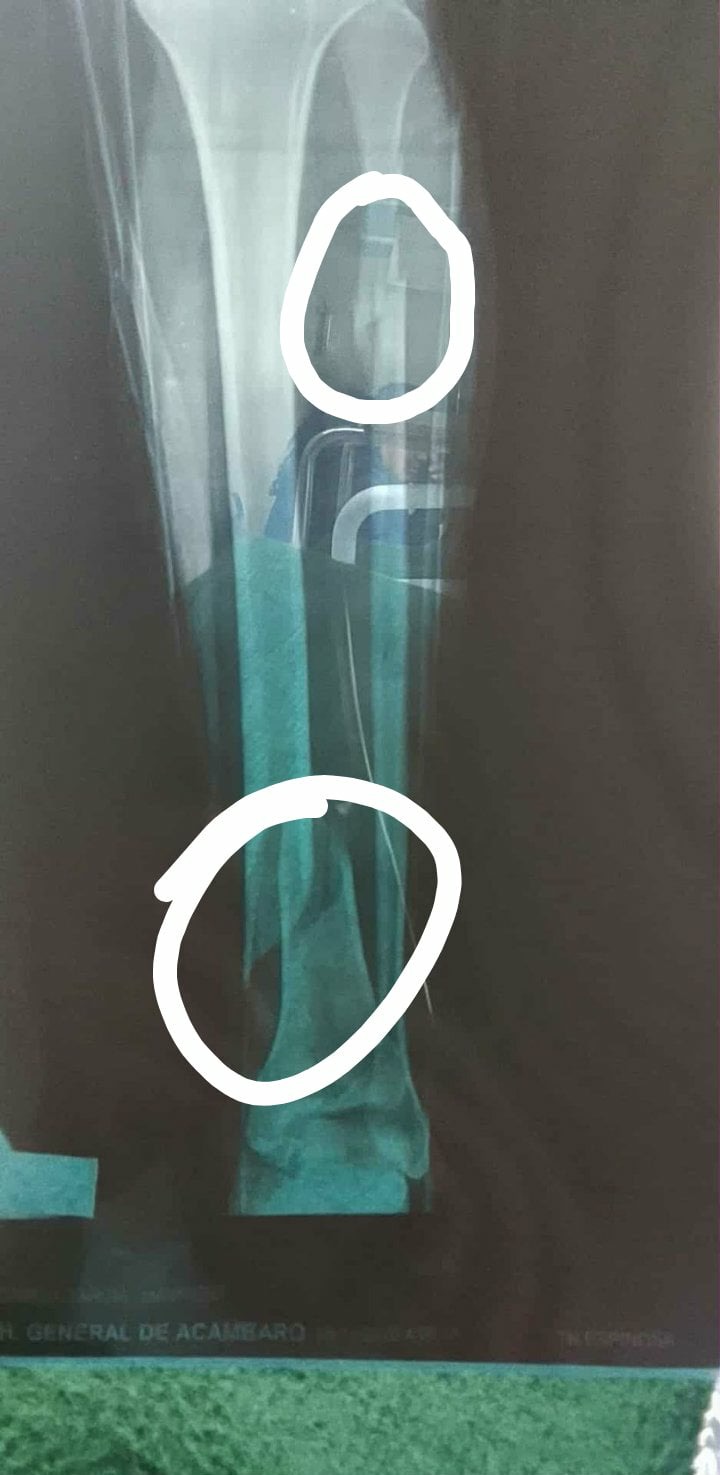

On November 7th, Mauricio fell and suffered several fractures in his leg, one of which requires emergency surgery. He hasn't received treatment because the hospitals can't perform the surgery since they don't have the money to pay for it.

El 7 de noviembre, Mauricio se cayó y sufrió varias fracturas en la pierna, una de las cuales requiere cirugía de emergencia. No ha recibido tratamiento porque los hospitales no pueden realizar la cirugía ya que no cuentan con el dinero para pagarla.